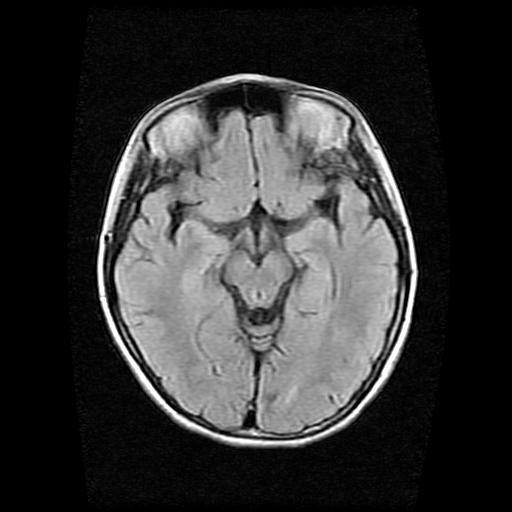

9岁女孩,三岁时诊断为癫痫,一直服丙戊酸钠,现患者一般情况良好,家长复查核磁片,看能否停药..

巨脑回